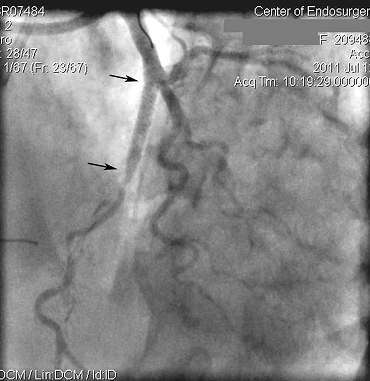

А вот как выглядят артерий сердца пациентки, которой предлагали операцию аорто-коронарного шунтирования. Вместо обходного кровотока, мы окрыли артерию, кровоток восстановлен естественным путем, т.е. как было до закупорки. Мы не вставили обходной шунт, а реконструировали собственный поврежденный сосуд сердца. Как видим на месте установки стента (протеза) просвет артерии выглядит прекрасно (показывают стрелки) и артерия уже видна на всем протяжении, т.е. кровоток осуществляется в полной мере, как и до закупорки.

Этот рисунок также показывает результат выполненного малоинвазивного лечения, но с другим углом зрения. Ранее закупоренная артерия полноценно заполняется кровью и снабжает участки сердца, которые ранее страдали от неполноценного кровоснабжения.